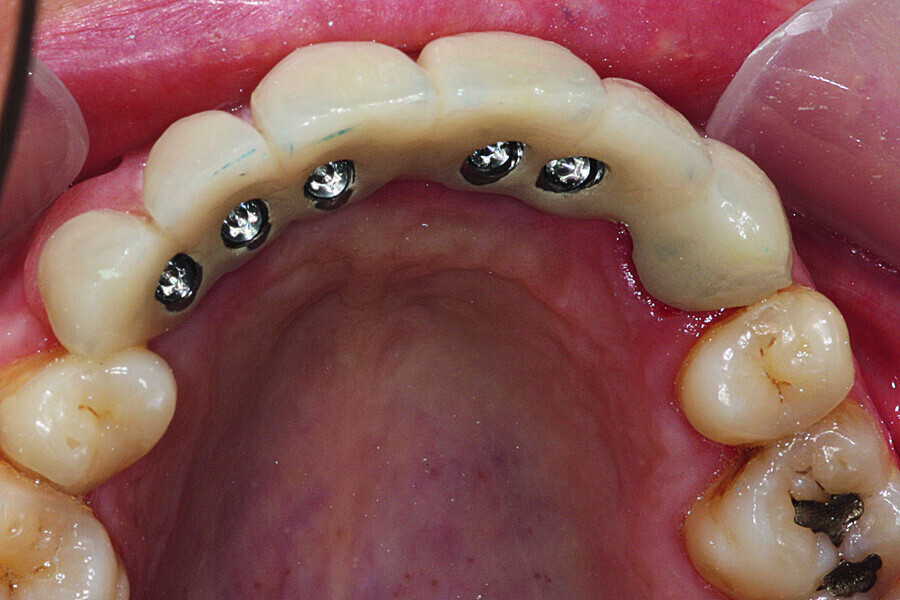

Fig. 36: Installation of the final prosthesis and verification of

correct occlusion. Screw channels filled with composite.

Fig. 37: Installation of the final prosthesis and verification of